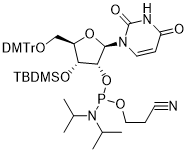

馬鞍山致研生物醫(yī)藥科技有限公司成立于馬鞍山市鄭浦港新區(qū)現(xiàn)代產(chǎn)業(yè)園。公司專(zhuān)注于生物小分子、醫(yī)藥中間體相關(guān)產(chǎn)品的研發(fā)和生產(chǎn),產(chǎn)品主要包括DNA亞磷酰胺單體、RNA亞磷酰胺單體、特殊單體以及按照客戶(hù)要求定制的RNA和DNA,并且公司提供定制合成等方面的研究服...

馬鞍山致研生物醫(yī)藥科技有限公司成立于馬鞍山市鄭浦港新區(qū)現(xiàn)代產(chǎn)業(yè)園。公司專(zhuān)注于生物小分子、醫(yī)藥中間體相關(guān)產(chǎn)品的研發(fā)和生產(chǎn),產(chǎn)品主要包括DNA亞磷酰胺單體、RNA亞磷酰胺單體、特殊單體以及按照客戶(hù)要求定制的RNA和DNA,并且公司提供定制合成等方面的研究服...